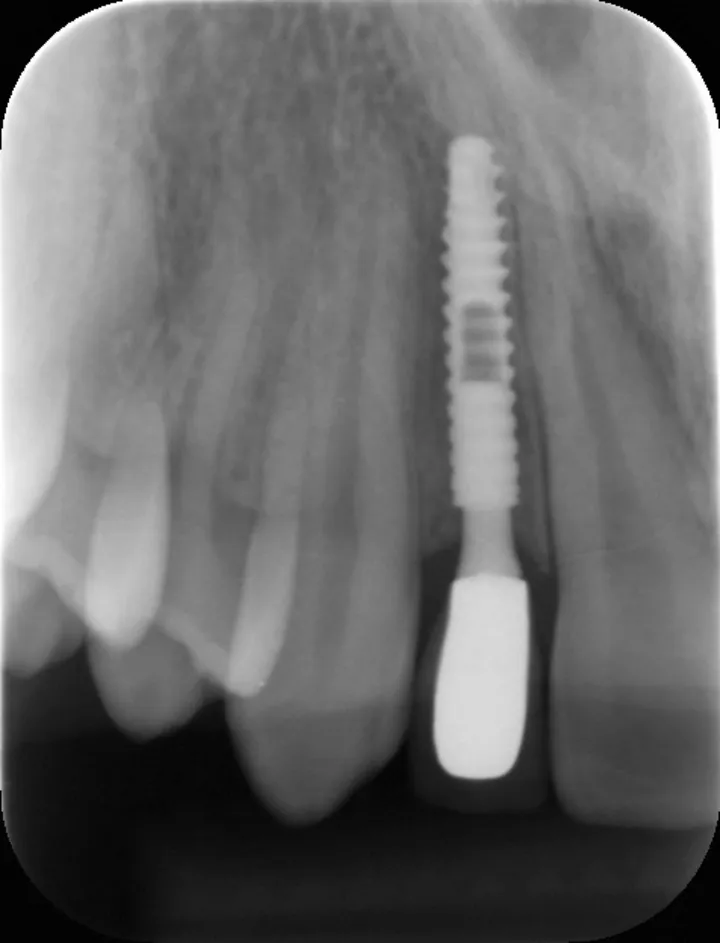

2 号病例 - Patrick EXBRAYAT 医生(图 21 至 35)

22 岁患者,23 异位,行正颌外科种植术后 22 出现严重根吸收。

图 26 :术后 X 线检查。

图 35 :术后 1 年随访 X 线影像。